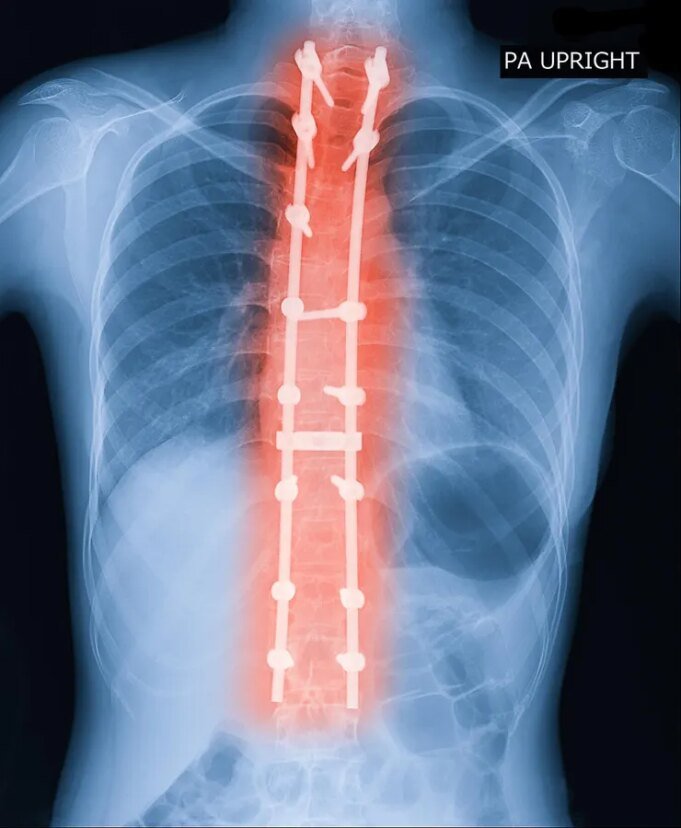

A escoliose lumptômica escoliosa (ASLS) cria um problema complexo em um atendimento suicitado, a qualidade aprofundada da dor, incapacidade e defesa. Essa situação é caracterizada pela curvatura lateral na coluna lamitada, diferindo dos adultos. Enquanto Scaum nasce, geralmente quando há crescimento, ocorre quando há uma extensão das alterações que levam as alterações degeneradas na região lombar. A dor é um sinal -chave na maioria dos casos de adultos, a maioria dos casos pediátricos. Além disso, devido a espinhos adultos, geralmente requerem técnicas não ópadas, como ostototomias ou cortes ósseos para obter a coluna vertebral.

Aprenda a informação II em conjunto com grupos em nove centros matinais americanos. Ele listou 286 adultos de 40 a 80 anos, o que inclui uma felicidade sintomática e 84 pacientes com cirurgia e 104 pacientes com cirurgia e 104 pacientes. A coleta e análise de informações serão coletadas entre novembro de 2023 e julho de 2024 e 2024 ocorreram em 72% em 8 anos. Este é um esforço do exército para rastrear os pacientes, incluindo aqueles que são para uma gestão maligna, é importante para o seu reitor e sua escala.

Os resultados dos resultados estabelecidos usando as medidas aprovadas, incluindo a deficiência do OUNDENI e o índice empoeirado individual da deficiência da deficiência da deficiência e da qualidade da vida. Pacientes com o surgimento fizeram resultados significativos mais que os pacientes 2, 5 e 8 anos. Deve -se notar que os pacientes com cirurgia experimentaram um evento negativo, em comparação com os locais do sensor, apesar dos perigos potenciais. Esses achados sugerem diretrizes para pacientes e clínicas, que são uma situação difícil.